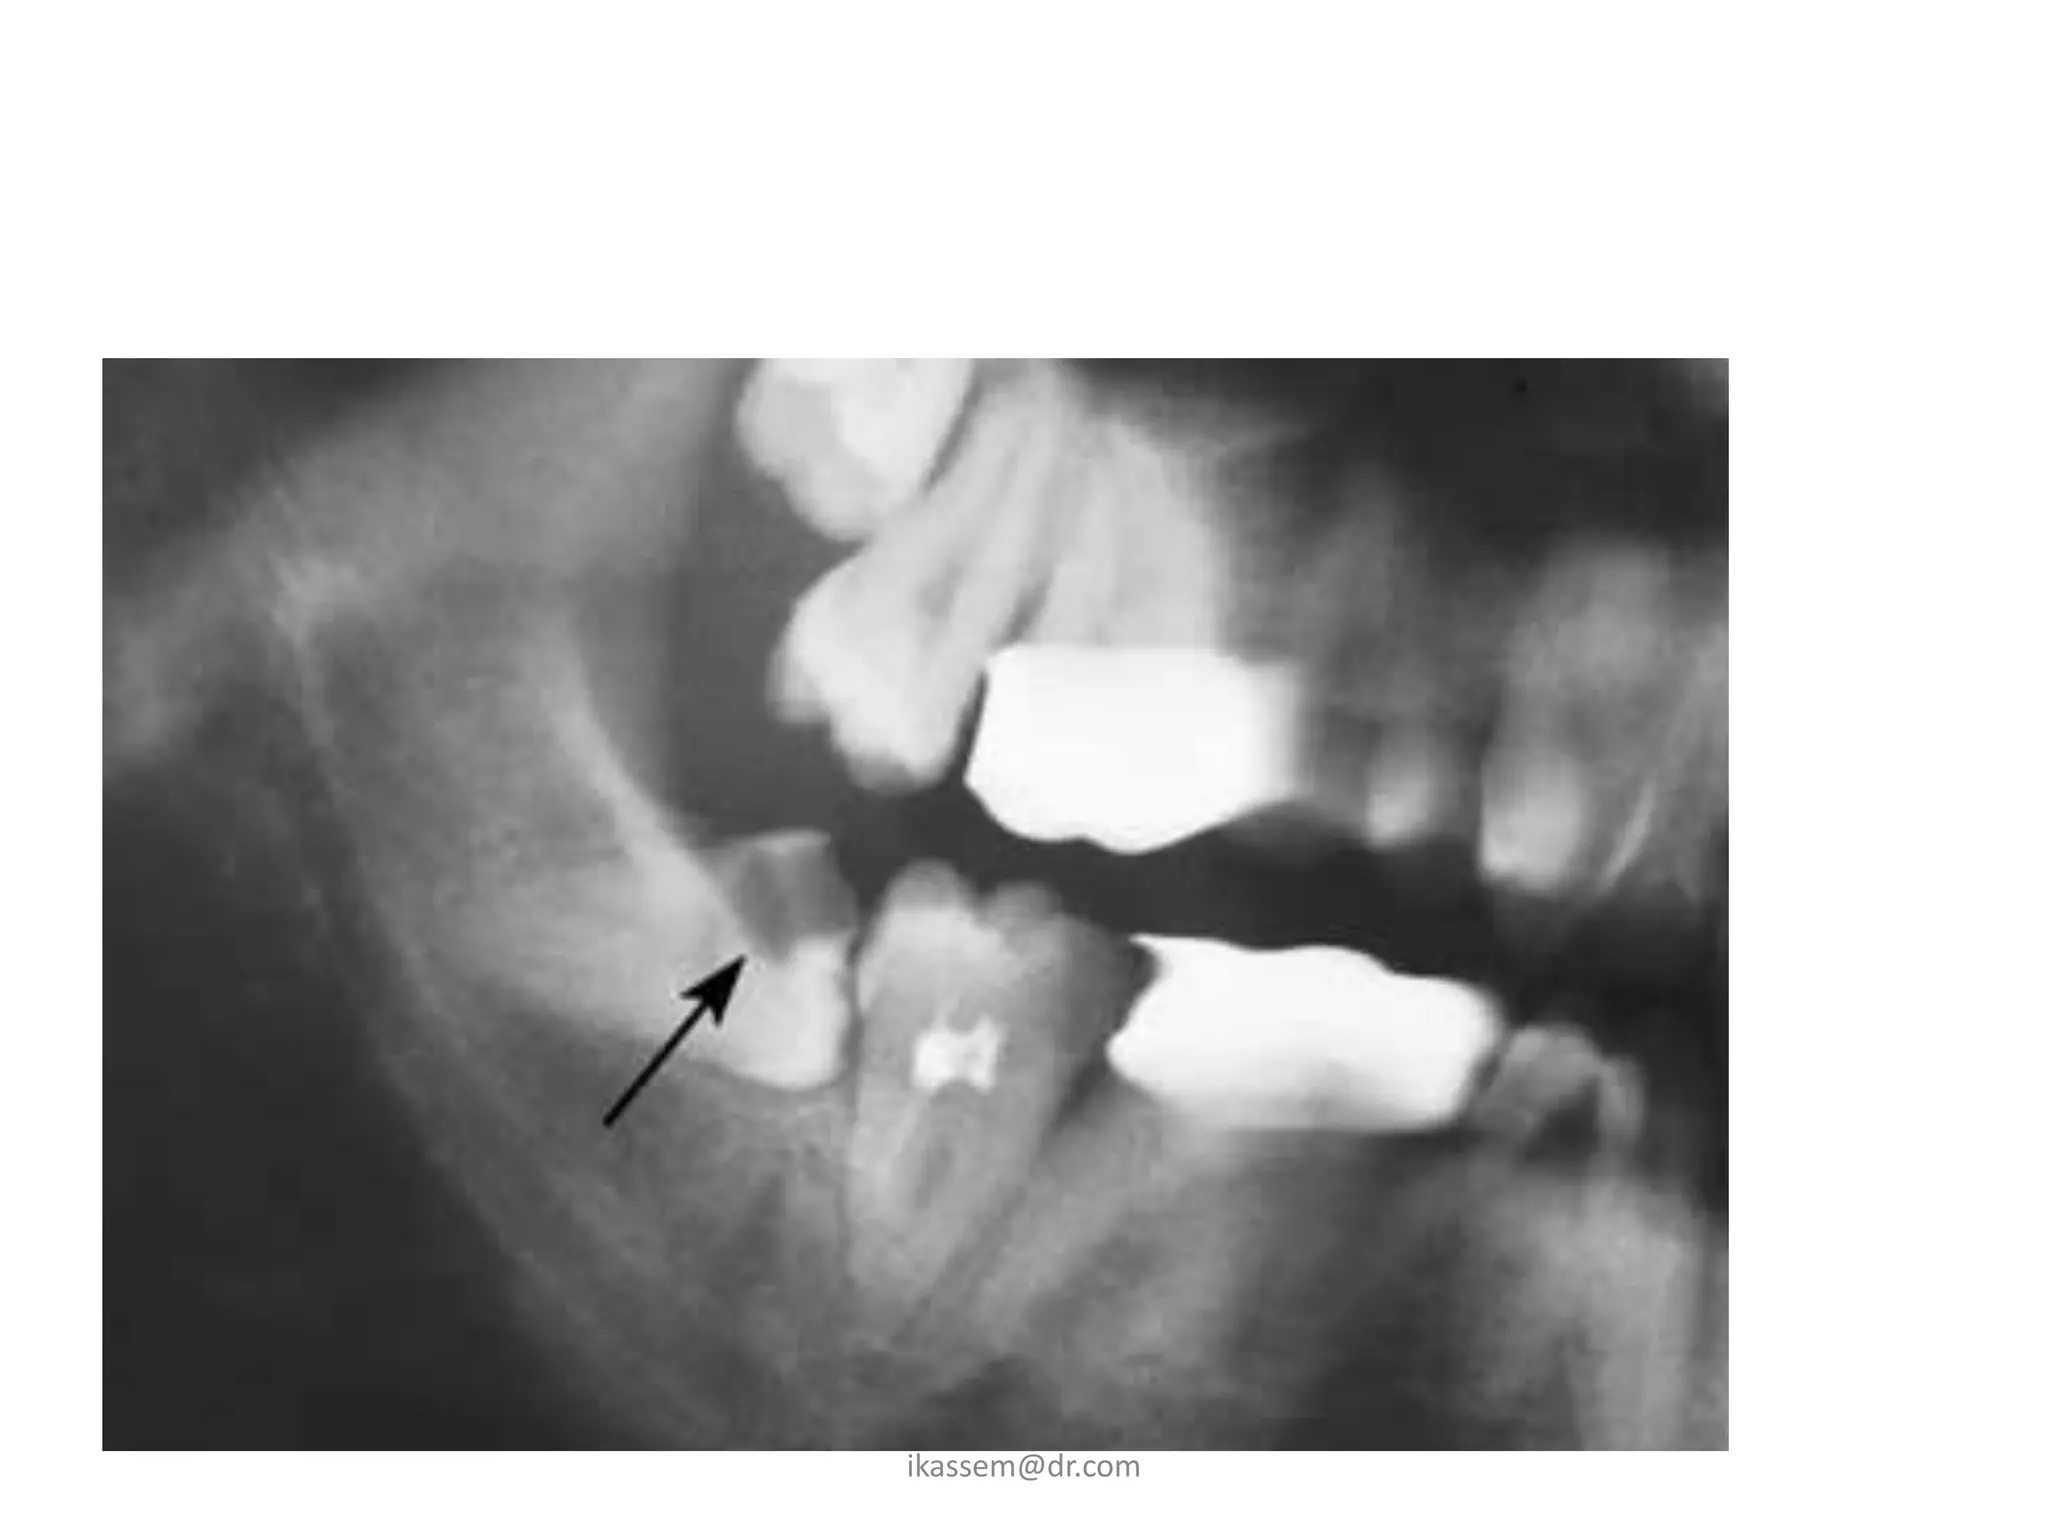

2 -Classification of impacted

maxillary third molar:

1.  The relationship of the tooth to occlusal plane of the 2nd

molar (as before)

2. The relationship of tooth to maxillary sinus :

a-sinus approximation :

(s.a) where no bone or very thin bone exist

between the impacted teeth and floor of sinus.

b-no sinus approximation :

(n.s.a) where 2 mm or more of bone exist

between the floor of sinus and impacted teeth.

3-Classification of impacted

maxillary cuspids:

• Class1:

palatally impacted cuspids ,these could be in vertical,

horizontal, semivertical position.

• Class2:

labialy impacted cuspide which could be in vertical,

horizontal, semivertical.

• Class3:

impacted cuspid located both in the palatal and labial

surfaces.

• Class4:

impacted cuspid that are present in an edentulous maxilla

and may assume any of the previous three classes.